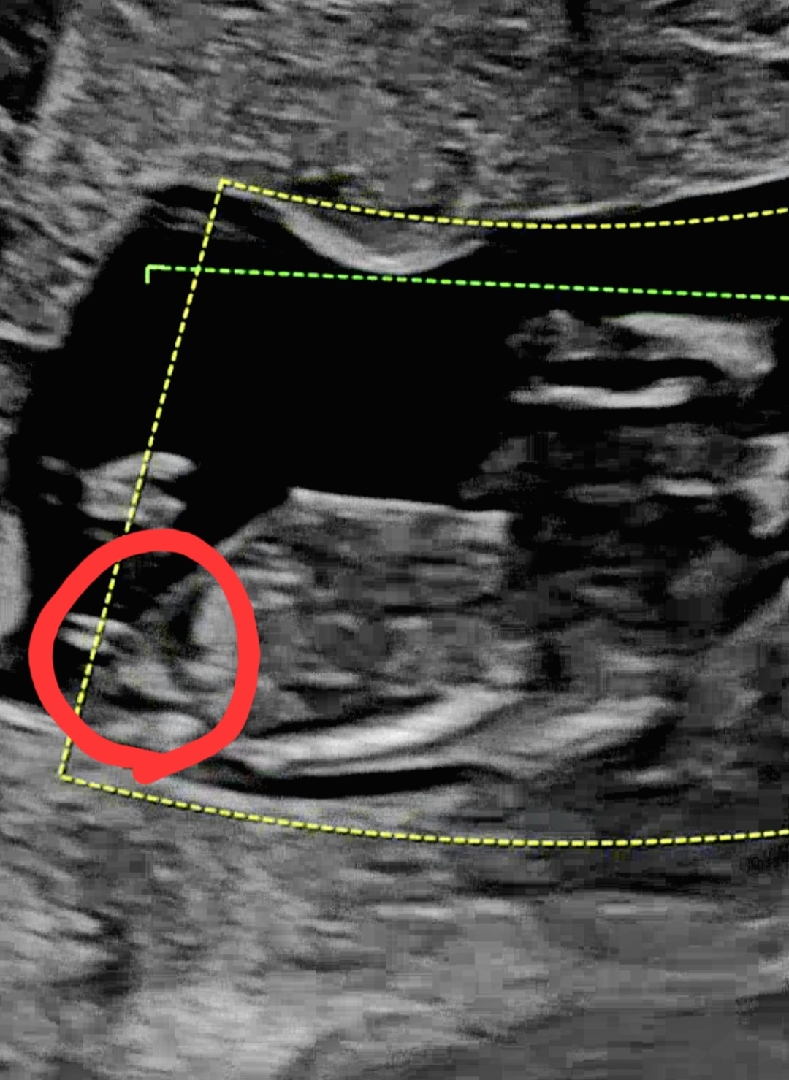

임신12주 초음파 아들일까요

아들 둘맘께서 초음파 보시고 아들이라고 하는데 저는 첫째는 딸이였으면 해서 ㅜㅜ ... 보시기에 아들처럼 보이나요??

움 뭔가 대가 짧고 갈라져서 아직 모를것 같긴해요!